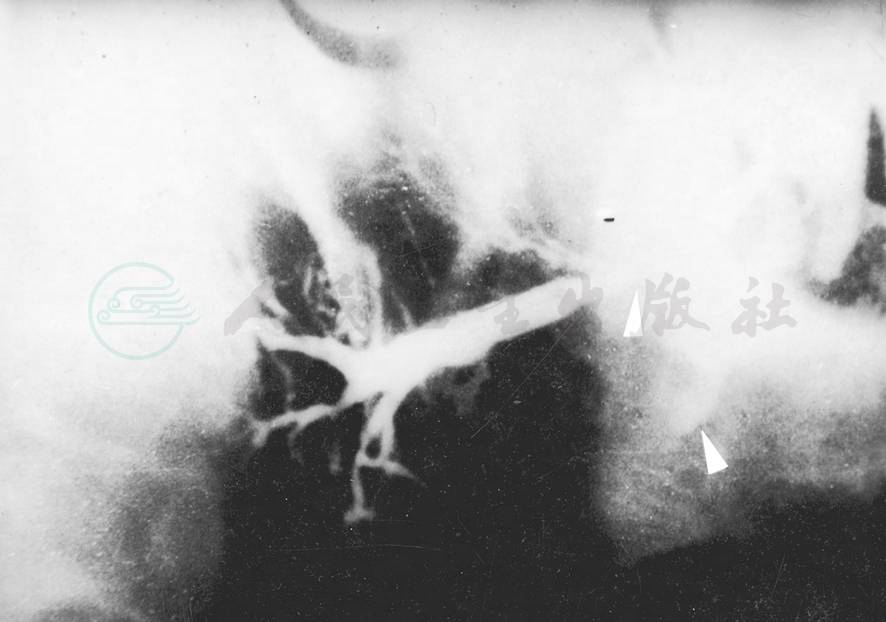

图2腮腺管瘘(腮腺造影侧位片)

上部“↑”所示导管狭窄中断;下部“↑”所示造影剂外溢

造影片上导管系统完好,只是腺体某处有造影剂外溢,则可诊断为腺瘘(图1)。如为管瘘则可见主导管上瘘口处有造影剂外溢,在其后方可见导管扩张不整,为瘘口处狭窄及继发感染所致(图2)。检查时尚须注意瘘口离腺门的远近,以便决定手术治疗方案。